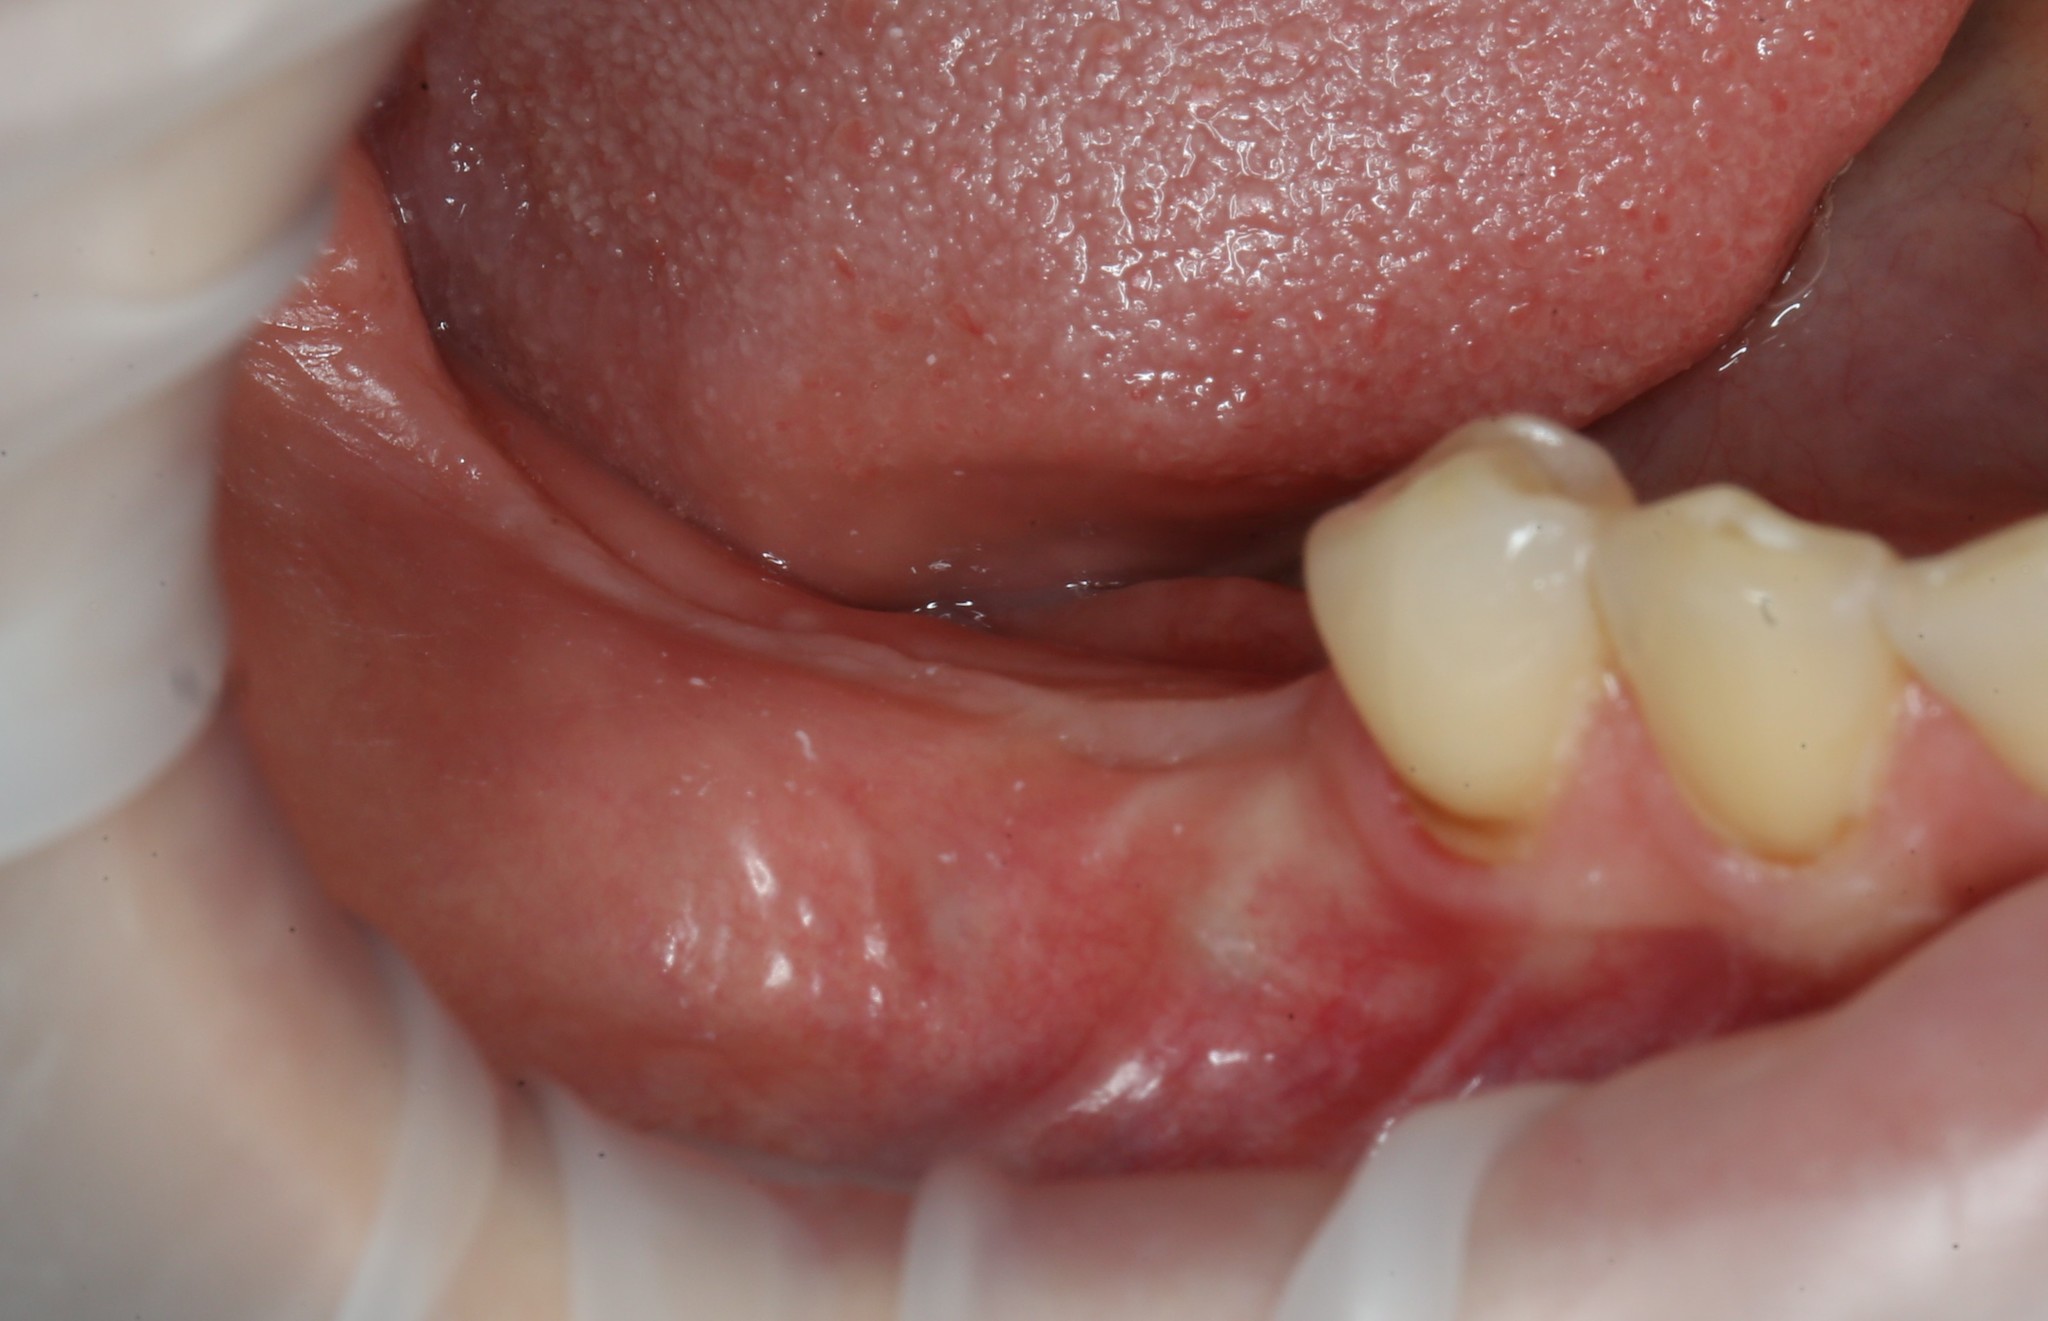

Итак, 5 месяцев позади: